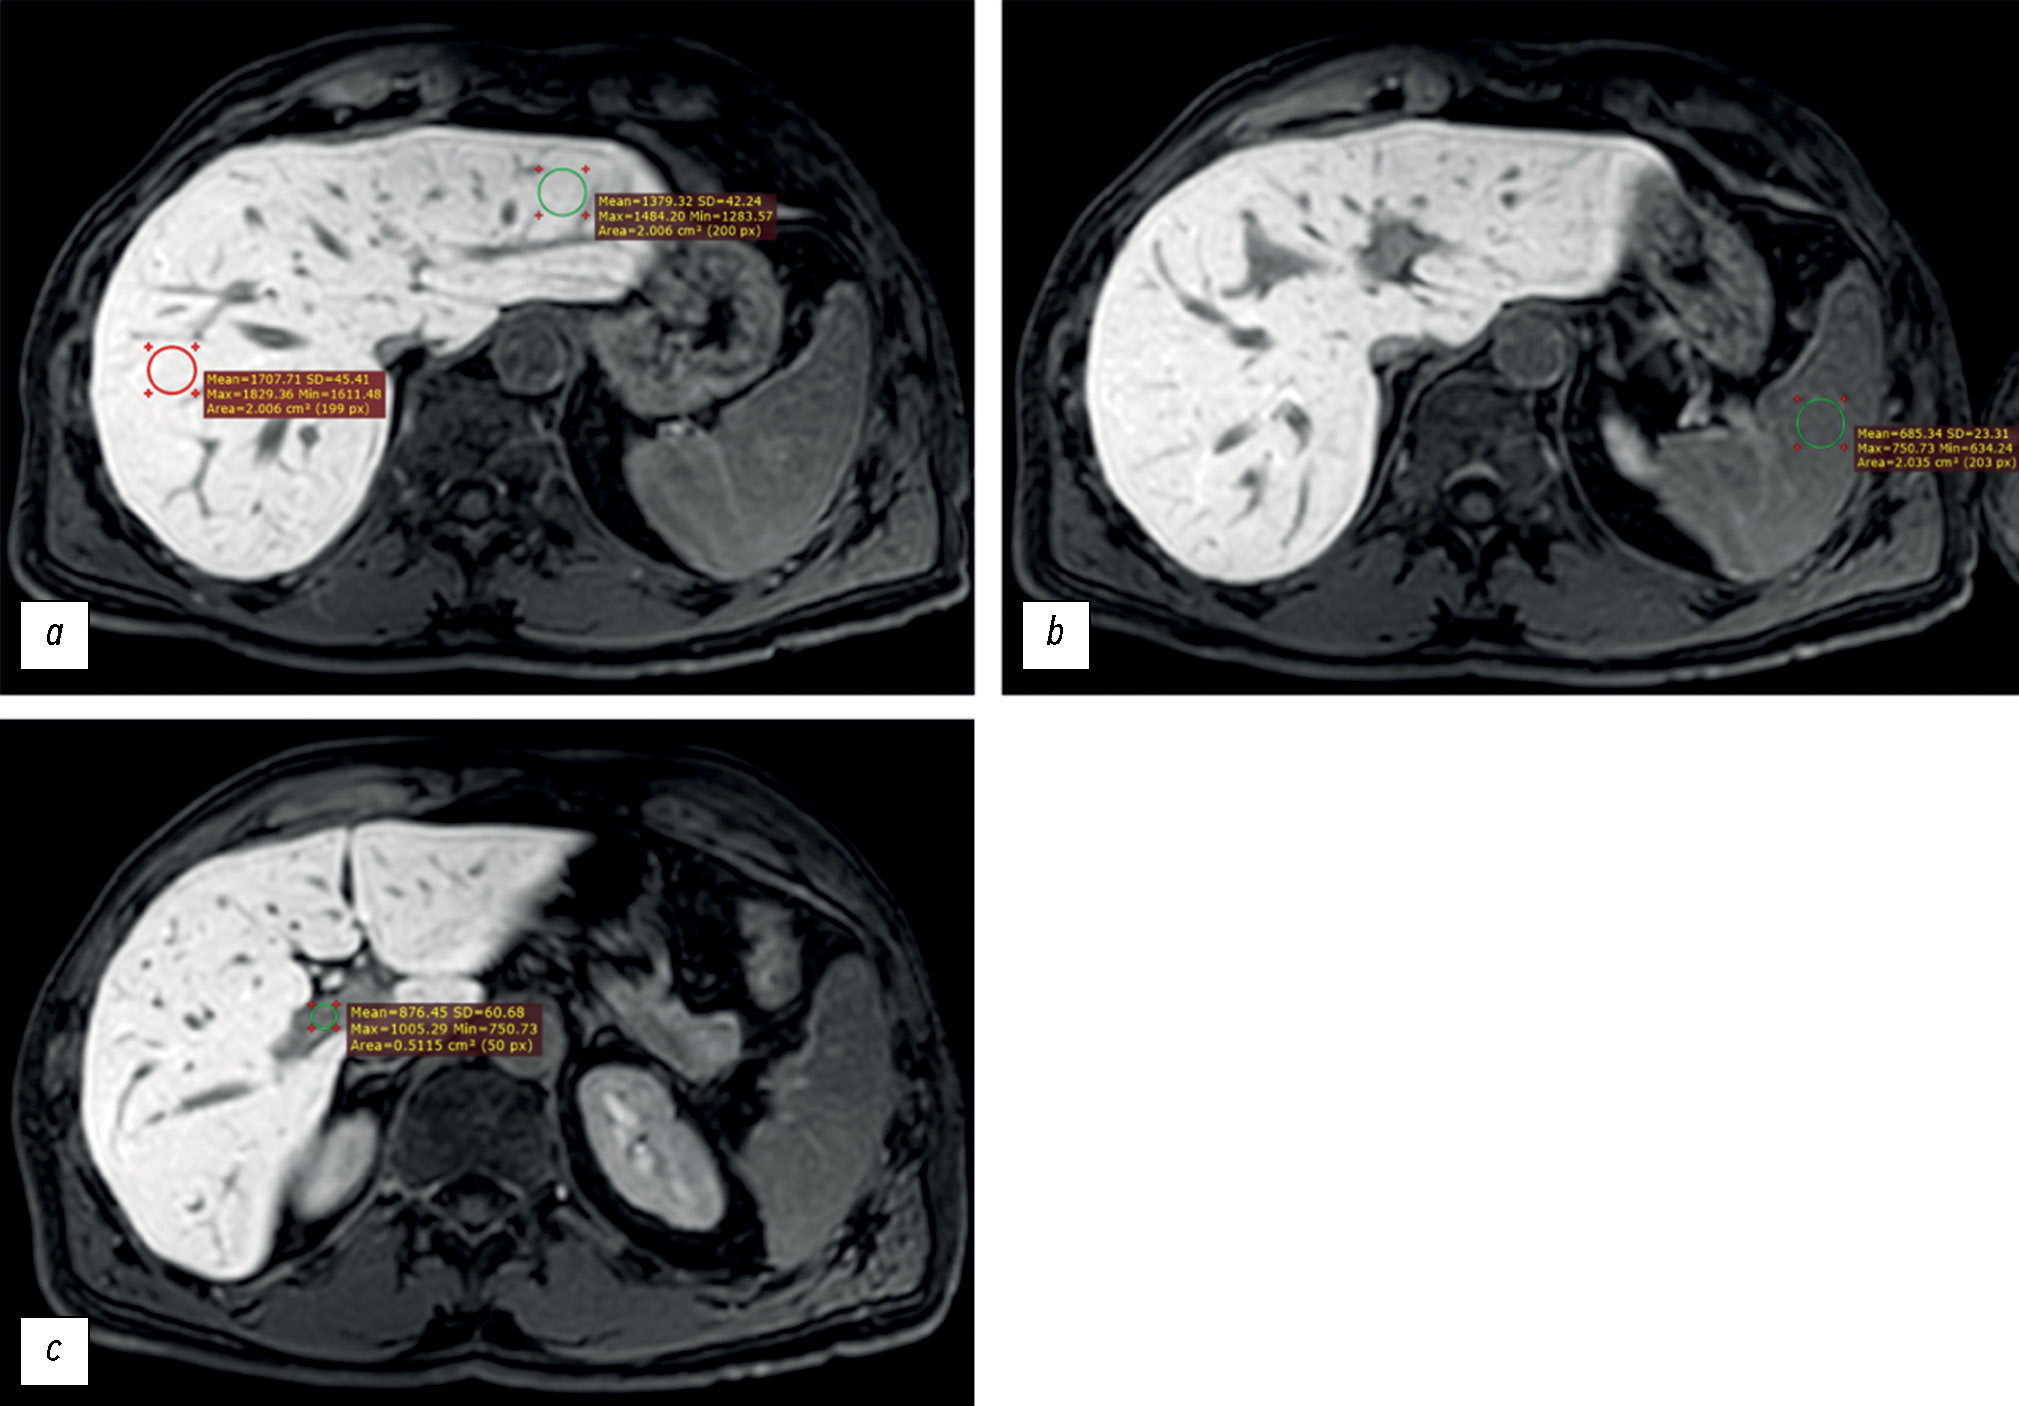

MATERIALS AND METHODS: Datasets of patients who underwent gadoxetic acid-enhanced magnetic resonance imaging were retrospectively reviewed. Patients were divided into two groups: group 1 included patients with impaired liver function, and group 2 included those with normal liver function. Based on magnetic resonance imaging in the hepatobiliary phase, the liver parenchyma signal intensity and its ratio to spleen signal intensity and portal vein signal intensity were estimated. Differences among these parameters were compared between groups. The correlation between liver parenchyma signal intensity and laboratory blood tests reflecting liver function (total bilirubin, albumen, aspartate aminotransferase, alanine aminotransferase, alkaline phosphatase, gamma glutamyl transpeptidase, and prothrombin time) were analyzed.

RESULTS: Datasets of 53 patients (25 men and 28 women, aged 24–84 years) were analyzed. Group 1 included 19 patients, whereas group 2 included 34. The median liver parenchyma signal intensity was 919.05 [669.65; 1258.35] in group 1 and 1525.13 [1460.5; 1631.4] in group 2 (p=0.0000001). The median ratio of liver parenchyma signal intensity to spleen signal intensity was 1.2 [1.04;1.7] in group 1 and 1.7 [1.46; 1.96] in group 2 (p=0.00076). The median ratio of liver parenchyma signal intensity to portal vein signal intensity was 1.44 [1.29; 1.83] in group 1 and 1.6 [1.43; 1.83] in group 2 (p=0.1). The estimated correlation values between liver parenchyma signal intensity and blood tests parameters were as follows: total bilirubin (r=–0.61; p=0.000001), albumen (r=0.13; p=0.61), aspartate aminotransferase (r=–0.57; p=0.000009), alanine aminotransferase (r=–0.44; p=0.001), alkaline phosphatase (r=–0.45; p=0.0007), gamma glutamyl transpeptidase (r=–0.5; p=0.0003), prothrombin time (r=–0.34; p=0.04).

CONCLUSION: The study reflects the ability to assess liver function using indices (liver parenchyma signal intensity and its ratio to spleen signal intensity) derived from gadoxetic acid-enhanced magnetic resonance imaging. However, this study did not confirm the assumed effectiveness of using the liver parenchyma signal intensity to portal vein signal intensity ratio as an index of liver function. A significant inverse correlation was identified between liver parenchyma signal intensity and blood test parameters in reflecting liver function, except for albumin. The results indicate the possibility of using magnetic resonance imaging to assess liver function.